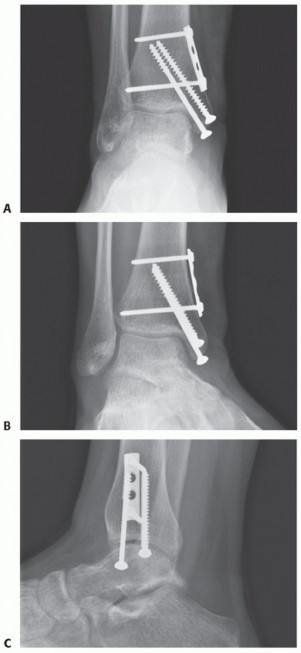

Débride the OLT sharply to stabilize circumferential rim of articular cartilage ( TECH FIG 3A ).

Be sure that the defect is contained.

Bony rim circumferentially

Interference fit will be compromised if medial talar dome at the defect lacks integrity. If not, then a structural allograft reconstruction should be considered.

Assess defect size and orientation with the sizing guide and with reference to preoperative CT scan ( TECH FIG 3B ). Larger defects may warrant two or even three grafts.

Recipient site chisel

Assistant will need to position foot in maximal inversion or eversion for medial and lateral OLTs, respectively ( TECH FIG 4A ).

Select appropriate chisel size.

Orient chisel perpendicular to defect ( TECH FIG 4B ).

We routinely advance the chisel 11 to 12 mm into the talus ( TECH FIG 4C ).

Maintain proper chisel orientation to the desired depth.

TECH FIG 3 • A. The surgeon probes and débrides the OLT to define its superficial dimensions. B. The defect is sized to determine optimal recipient chisel size. Do not attempt to change orientation of the chisel once the chisel has been advanced into the subchondral bone.

Once at the desired depth, twist the chisel forcefully 90 degrees and then 90 degrees again ( TECH FIG 4D ).

Gently toggle the chisel to free the diseased cartilage from the surrounding healthy cartilage. Extract the diseased osteochondral cylinder ( TECH FIG 4E ).